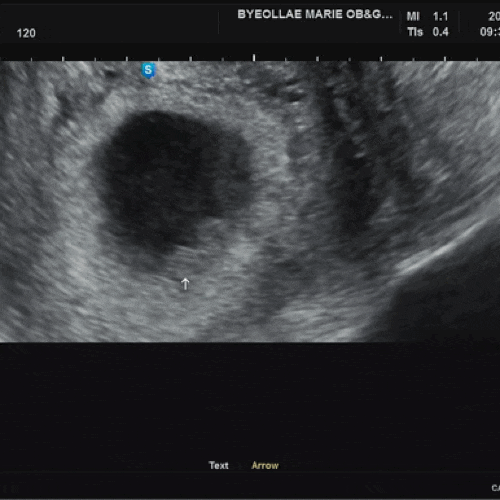

오늘로 임신 6주 5일차가 되었다. 5주 4일부터 시작된 입덧. 겨우 일주일이 되었을 뿐인데 일주일이 마치 7...